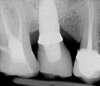

L’image radiologique post-opératoire montre les deux implants ancrés dans la poudre d’os qui a servi à combler le sinus maxillaire.

L’image en 3 dimensions indique que la hauteur disponible d’os est de 7 mm

La simulation implantaire indique que la hauteur d’os à gagner est de 3 mm pour placer un implant de 10 mm

L’image 3D de contrôle post-opératoire montre le gain obtenu par le soulèvement sinusien